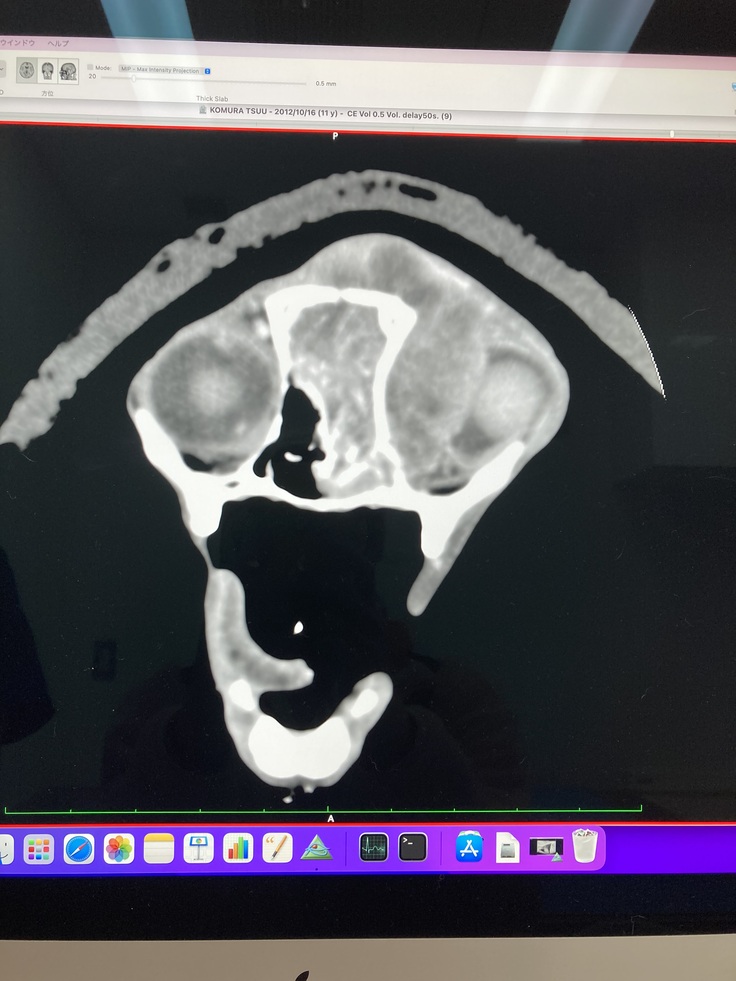

CT画像

←右目 左目→

(画像上側がおでこ辺りになります。左目が腫瘍によって押しつぶされている状態です)

腫瘍によって、脳の形にも変形が見られています

脳みその真ん中の線が大きく左側(右目方向)にズレているのが分かります。